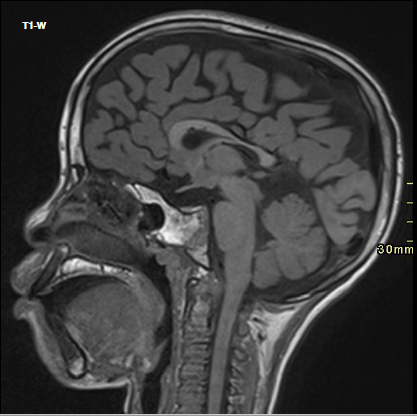

Introduction aux maladies de la substance blanche basic

BOITSIOS M. – ULB

Année académique 2021-2022

Nerveux Pédiatrique DES SPECIALITE